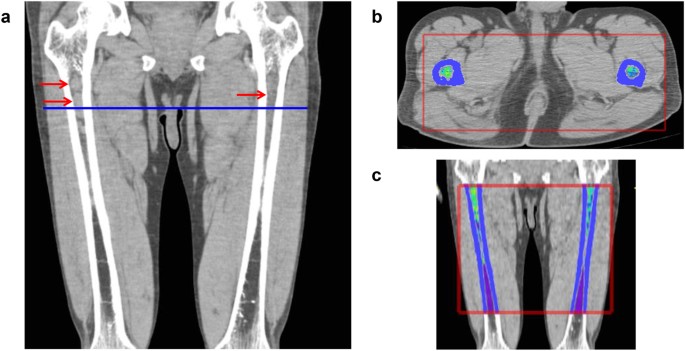

To determine a three-dimensional volume-of-interest and calculate the sum of CT values in one appendicular skeleton, the software set horizontal and vertical ranges on axial CT images. The horizontal range (x and y-axis) (e.g., shown as the red rectangle in Fig. 1b) included a bone marrow area surrounded by circular cortical bone. The software automatically recognized circular regions with CT values higher than 120 HU as cortical tubular bones. The vertical range (z-axis) (e.g., shown as the red rectangle in Fig. 1c) was anatomically defined by the operators to include the diaphysis and proximal and distal metaphysis and to exclude the proximal and distal epiphysis, as the trabecular architecture of the epiphysis expresses very high (over 120 HU) CT values. Once horizontal and vertical ranges in each appendicular skeleton had been selected, the software automatically extrapolated the ranges rest of the slices, and calculated cCTv for all the voxels within the selected bone.

Representative images of a patient with advanced IgAκ myeloma. (a) Coronal CT image of the femora. Myeloma infiltration was detected in the upper metaphysis and diaphysis in both the left and right femora (arrows). (b) Axial image at the level of the blue line shown in (a). The software provides pseudo-colour according to the Hounsfield unit (HU) (high: yellow-red, low: blue-purple). (c) Coronal image reconstructed from the axial slices. Red rectangle: horizontal and vertical ranges for the determination of cumulative CT value (cCTv). The cCTv of this case was 4.46 HU.